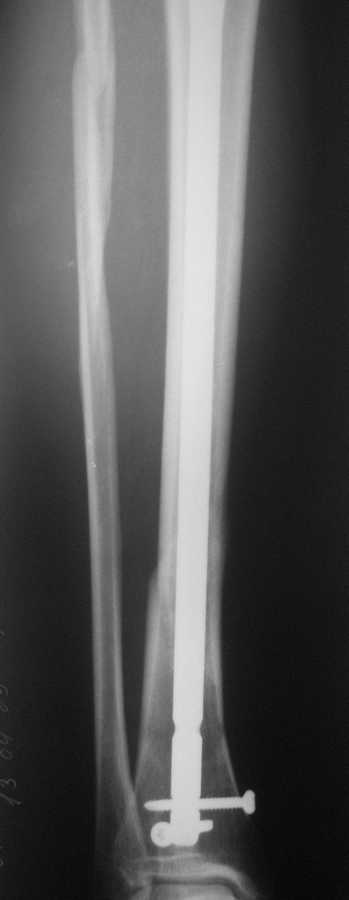

В январе 2009 года нами оперирована пациентка с переломом н\3 голени штифтом Expert. Динамизация через 4 месяца, пациентка при этом уже ходила с тростью. Дома периодически передвигалась без дополнительной опоры. В настоящее время - через 9 месяцев с момента операции периодически в вечернее время беспокоят ноющие боли в места перелома (не постоянно). При беседе выяснено, что боли чаще беспокоят после того, как днем она походит по дому без трости. Пальпаторно по гребню берцовой кости болей нет, но по задне-внутренней поверхности б\б кости пальпирутеся западение на уровне места перелома.В чем ошибка??? и что делать???

Недостаточная стабильность. Не использованы все возможности дистального запирания, нет самого проксимального из дистальных винтов. Два винта из трех коротковаты. В результате при диинамизации появился диастаз.

Тут есть уже опасность перелома стержня по ближайшему к перелому отверстию. Так что правильнее сделать реостеосинтез с рассверливанием. При введении гвоздя в дистальный отломок использовать отклоняющую спицу

или винт, чтобы стержень оказался не у переднего кортекса, как сейчас, а где и надо - посередине. Это обеспечит еще и встречно-боковую компрессию.

Значит, изначально в периферическом отломке гвоздь шел не по центру, а ближе к передней стенке. Это не очень хорошо.

Да, динамизация поздновата. Да дистальный отломок заперт одним винтом, два другие короткие, еще дно отверстие пустое...

Этот 9-ти мм. стержень ExpertTN вряд ли скоро сломается, если, конечно же, пациентка не имеет большого веса (>100 kg). Перештифтовать более толстым штифтом с рассверливанием, пожалуй, самый надежный вариант, но не факт, что единственный. Вполне правомочно подумать просто о косой остеотомии малоберцоыой кости (зачем резекция???) в средней 1/3 и попытке дополнительной стабилизации дистального отломка путем запирания штифта через свободное отверстие (наиболее проксимальное из дистальных) и замены двух самых дистальных винтов, причем косой самый дистальный лучше провести в другой плоскости. Возможно этого будет вполне достаточно для сращения...а вот периодически возникающие боли могут и остаться(((

По снимку гвоздь сидит плотно в узкой части большеберцовой, а на периферии нестабильная блокировка. Динамизация работает в течение первых 8 недель.